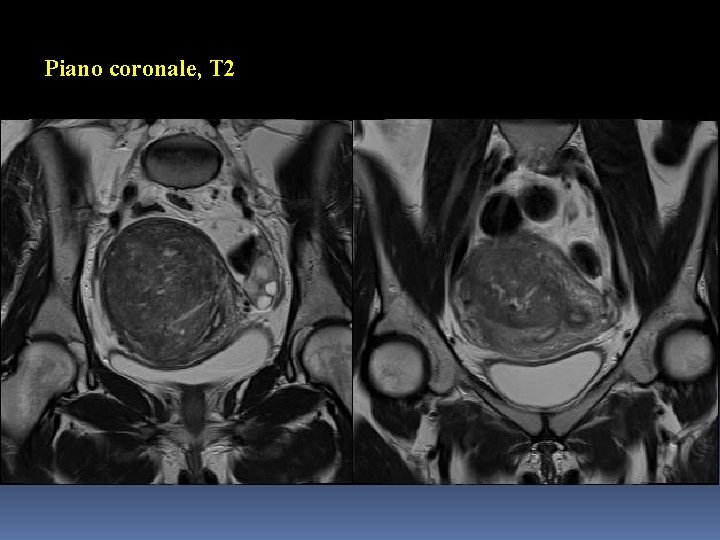

Piano coronale, T 2

Somiglianze Lesioni di grandi dimensioni → utero ingrandito e globoso Epicentro nel miometrio Segnale prevalentemente ipointenso in T 2 Assenza di grasso endolesionale Comportamento non significativo in DWI/ADC (diffusività non significativamente ristretta, cellularità poco aumentata)

Differenze (1) Interfaccia con il miometrio contiguo/visibilità e caratteristiche dei margini pseudocapsula/margini riconoscibili e netti nel Caso 1 interfaccia mal identificabile/margini sfumati nel Caso 2 Estensione, sede e rapporti anatomici lesione unica (focale) coinvolgente l’intero spessore del miometrio nel Caso 1 processo diffuso coinvolgente la zona giunzionale nel Caso 2

Differenze (2) Segnale in T 2 aree endolesionali modicamente iperintense e a margini non netti nel Caso 1 areole endolesionali iperintense e a margini netti (microcisti) nel Caso 2 Segnale in T 1 Fat sat isointenso con il miometrio nel Caso 1 con isolate areole a contenuto ematico nel Caso 2

Caso 1: immagini-chiave Pseudocapsula

Caso 1: immagini-chiave Areole endolesionali a margini sfumati, assenza di sangue

Caso 1: diagnosi Mioma in utero setto

Mioma I miomi o fibromi sono tra i più comuni tumori ginecologici (incidenza di circa il 70 -80% nelle donne in età fertile) e prendono origine dal miometrio. Tumori benigni, a causa ignota, costituiti prevalentemente da fibre muscolari lisce e, in proporzione variabile ma in genere inferiore, da tessuto connettivale. Sprovvisti di una vera e propria capsula, sono delimitati da una pseudocapsula; hanno margini netti e regolari.